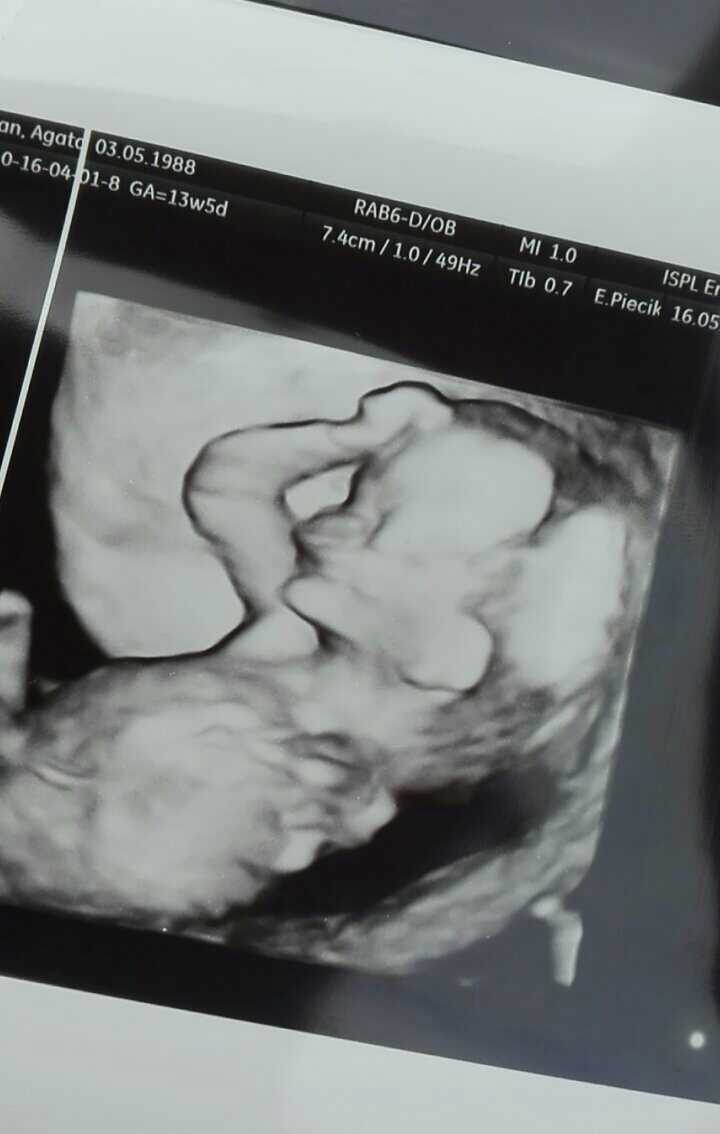

O kurcze ale super !!!Mój synek :-) :-) :-)

Pewnie dlatego, ze to zdjecie twarzy. Z raczka. Dzidzius trzyma sie za gloweO kurcze ale super !!!dr sie zna wiadomo bo ja tu pitoka za Chiny nie widze

MartiniMi jakbys na tym zdjęciu pitoka zobaczyla to szacunPewnie dlatego, ze to zdjecie twarzy. Z raczka. Dzidzius trzyma sie za glowe

Mój synek :-) :-) :-)